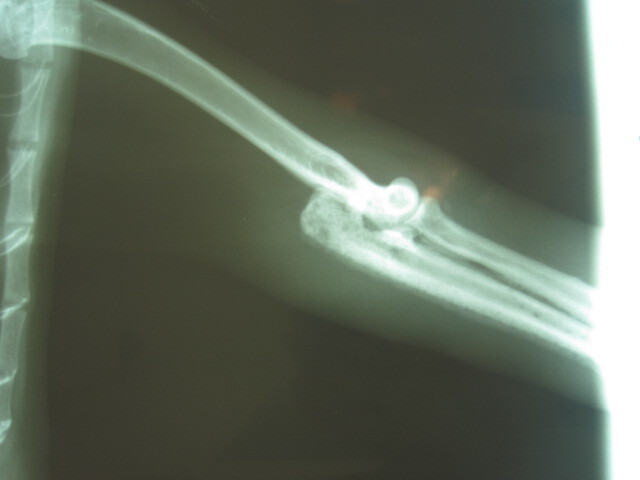

主題: 捕獸夾夾傷 需要截肢的貓咪 申請者姓名: 岳丹楓 花色: 申請日期: 2012-05-12 22:55:28 申請者部落格: 申請者臉書網址: 所在縣市/合作醫院: 台北市/詠欣動物醫院 治療費用: 9200元 需求人數: 11人 已結案 (2013-02-05 18:44:34) 報名人員: Ruth Chang(已付款)、suxiwen(已付款)、suxiwen(已付款)、Carol Su(已付款)、Kay Chiu(已付款)、hakumaio(已付款)、Larry Hey(已付款)、謝佩芳(已付款)、Yuan-Hsin Kuo(已付款)、Ellen Chiang(已付款)、Vanna Tai(已付款)、 候補人員: 小舟、小舟、小舟、 動物病情說明: 這隻已經TNR的貓咪,前幾天被義工李媽媽發現前腳掌被捕獸夾夾住.先送到附近動物醫院截肢.但因傷口感染,組織腫脹.改送到詠欣動物醫院醫治.檢查之下,發現有貧血 骨髓炎和輕微敗血.經二次截肢後,貓咪已經食慾正常.傷口復原良好.目前已出院 由李媽媽中途照顧.